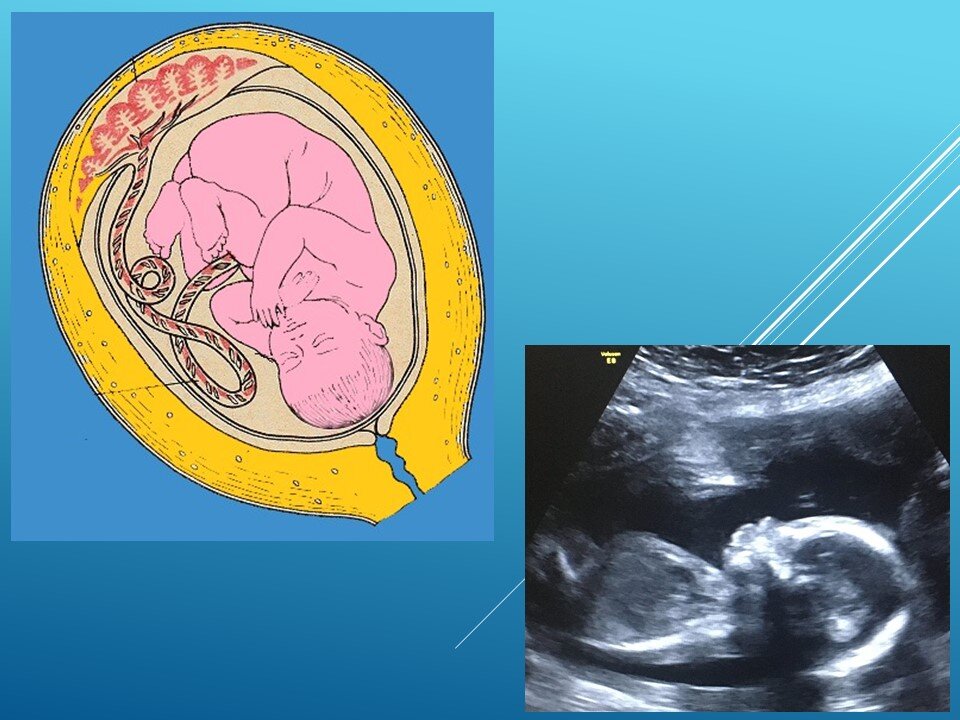

А теперь хочу рассказать Вам о том, какие ощущения испытывает будущий малыш, находясь в утробе матери. Думаю, что многие будущие мамочки рано или поздно задумываются об этом.

Коллаж автора